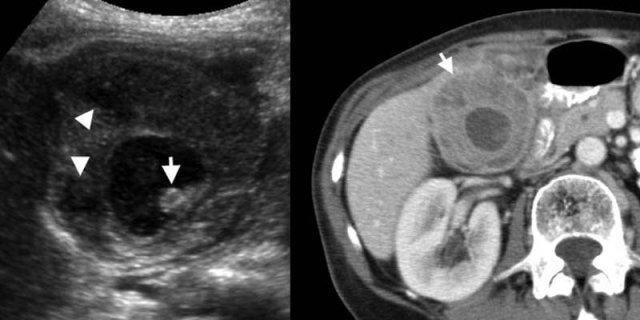

TRÁI: Siêu âm ở phụ nữ 59 tuổi bị viêm túi mật cấp cho thấy hình ảnh phân lớp của thành túi mật dày, với vùng giảm âm giữa các đường tăng âm. PHẢI: Trên CT có thuốc cản quang, túi mật thành dày chứa lớp ngoài giảm tỷ trọng (mũi tên) do phù nề dưới thanh mạc.

Thành túi mật dày

Thành túi mật được coi là dày khi đo hơn 3 mm, thường có hình ảnh phân lớp trên siêu âm [1], và trên CT thường chứa một lớp giảm tỷ trọng của phù nề dưới thanh mạc có thể nhầm lẫn với dịch quanh túi mật [2].